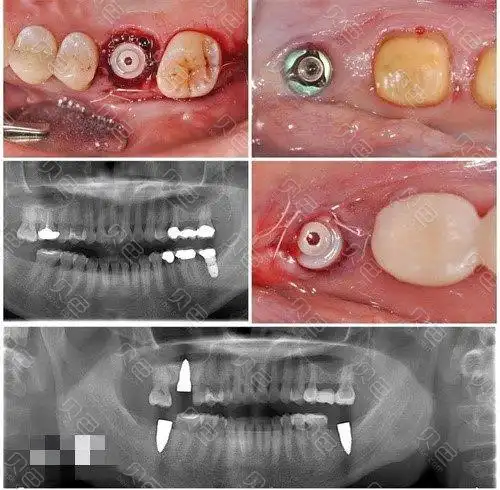

这些都是广州暨大穗华口腔荔湾院区的半全口种植牙病例

即刻拔牙后做半口瑞士士卓曼钛锆亲水种植牙,花了8.8万